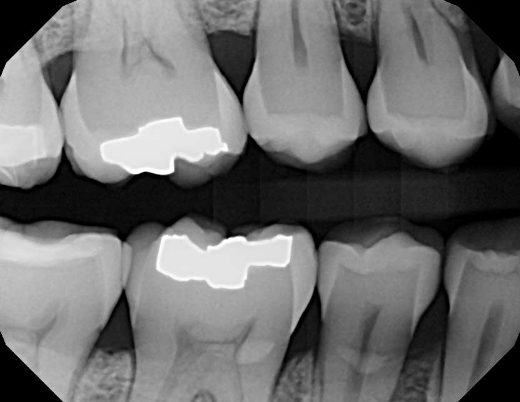

Interproximal x-rays, also known as bitewings, show the crowns of the upper and lower teeth; it helps the dentist to detect cavities between the teeth at the back of your mouth and evaluate the level of the supporting bone structure.